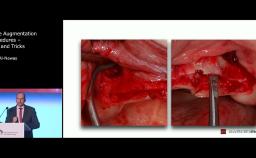

Minimizing the Risks in Maxillary Sinus Floor Elevations by Using Piezosurgical Technology

This lecture is brought to you by our industry partner mectron. It discusses lateral and crestal maxillary sinus floor elevation with a special emphasis on radiographic pre-operative planning to detect potential risk factors. It also highlights the importance of piezosurgical technology to augment surgical efficiency and to reduce perioperative complications.

- understand the step-by-step clinical procedures of both crestal and lateral sinus grafting techniques and the advantages of piezosurgery to minimize complications